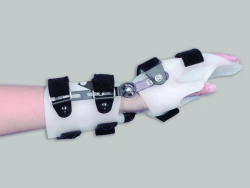

Wrist Joint Rehabilitation Device AR2-10-OK

US$90-300

Apparatus weight:

1

Material:

no

ORTO-KOSMOS LLC 🇷🇺